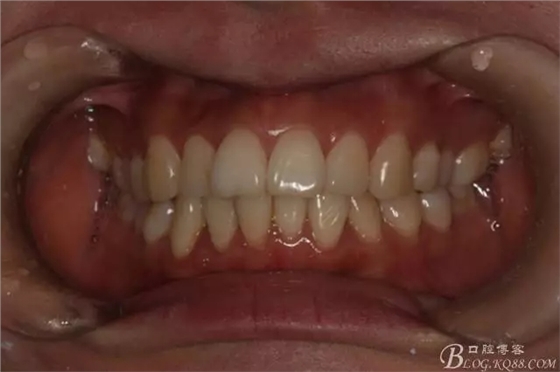

患者,女,主訴:牙齒不齊。

如圖,該病例為簡(jiǎn)單排齊病例,但77鎖合是矯治中的關(guān)鍵所在,你會(huì)怎么處理?